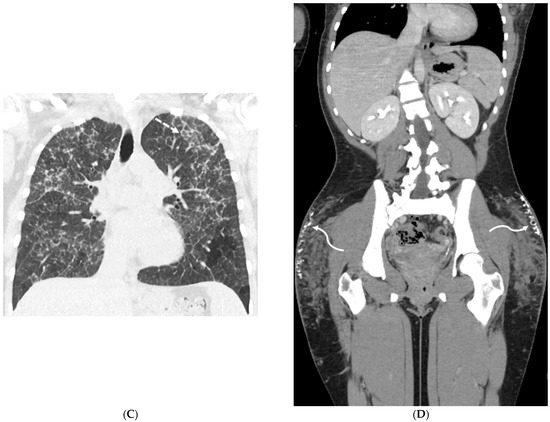

4.7. Pulmonary Vein Stenosis (PVS)